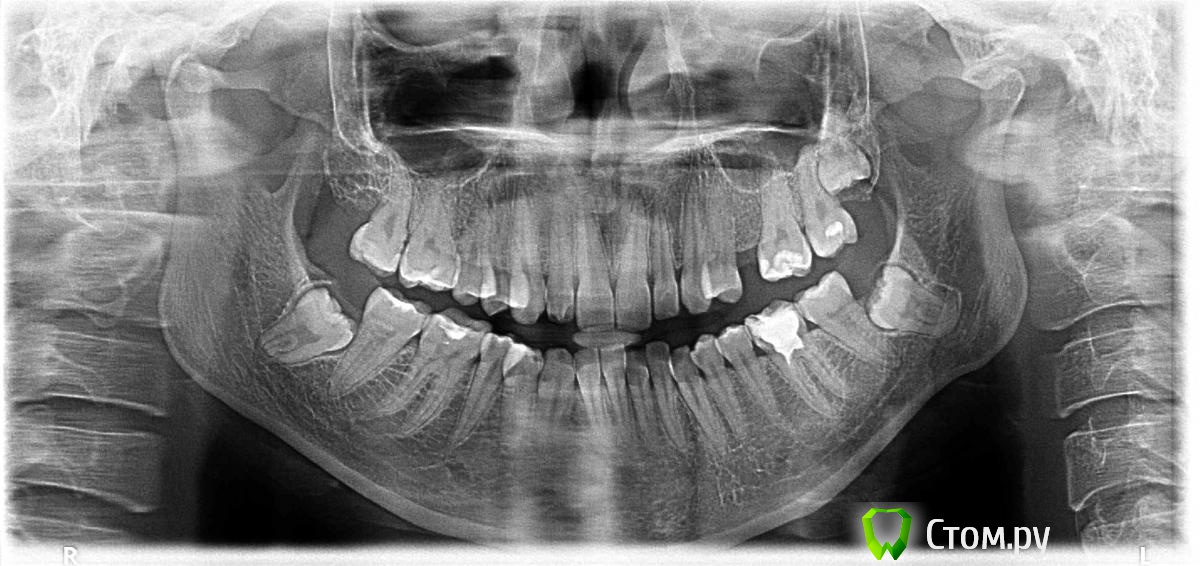

Асем Опубликовано 3 апреля, 2014 Поделиться Опубликовано 3 апреля, 2014 Здравствуйте!хотела проконсультироваться. была у ортодонта, она мне сказала поставить брекеты. так как идет смешение. сделала снимок. сказали надо удалить зубы мудрости. но, они у меня под деснами. теперь вопрос нужно ли мне удалять зуб мудрости? или брекеты и потом можно удалить зубы? как быть? Ссылка на комментарий

red_butler Опубликовано 4 апреля, 2014 Поделиться Опубликовано 4 апреля, 2014 (изменено) удалить все три 8-ки???да, все три, окончательно решит ортодонт. Зуб 4.6 (шестой внизу слева) до ортодонтии перелечить у эндодонтиста Изменено 4 апреля, 2014 пользователем red_butler Ссылка на комментарий

Фазлиев Азат Ильдусович Опубликовано 5 апреля, 2014 Поделиться Опубликовано 5 апреля, 2014 да, все три, окончательно решит ортодонт. Зуб 4.6 (шестой внизу слева) до ортодонтии перелечить у эндодонтистаДумаю произошла опечатка- зуб 3.6 Ссылка на комментарий

red_butler Опубликовано 5 апреля, 2014 Поделиться Опубликовано 5 апреля, 2014 Думаю произошла опечатка- зуб 3.6спасибо, конечно 3.6 Ссылка на комментарий